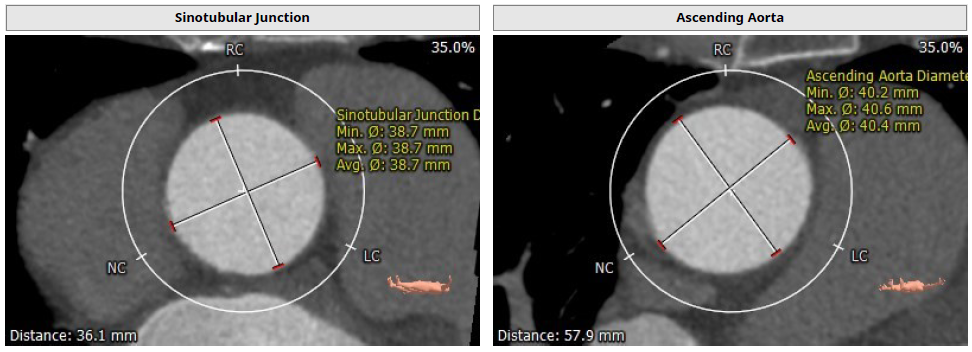

影像分析

患者主动脉瓣三叶式,瓣叶基本大,瓣膜轻度增厚,右冠瓣瓣叶边缘轻度钙化;主动脉瓣环周长折算直径28.4mm;双侧冠脉开口高度可LCA:12.4mm,RCA:25.0mm;术中造影角度RAO:4°,CAU:3°。